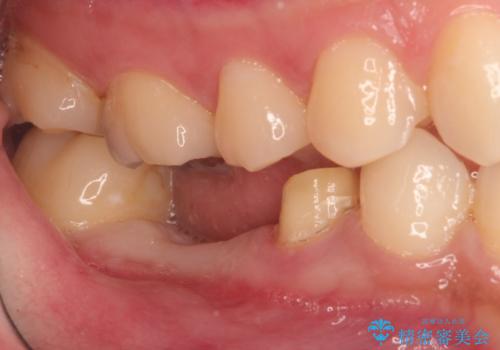

- 右下の奥歯の調子がよくないとのことで来院されました。

レントゲン・口腔内診査をお行い、保存が難しいことがわかりました。

抜歯後インプラントをする計画としました。